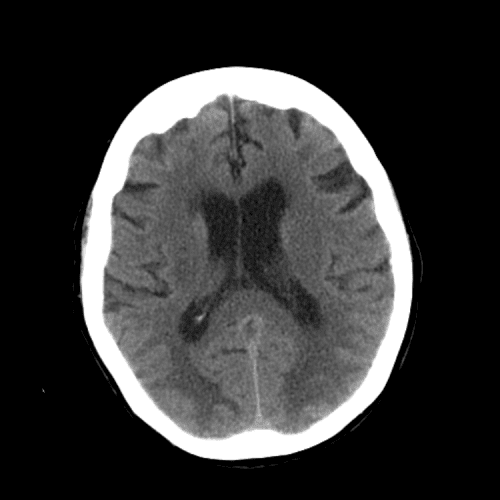

ACA and MCA territory infarct